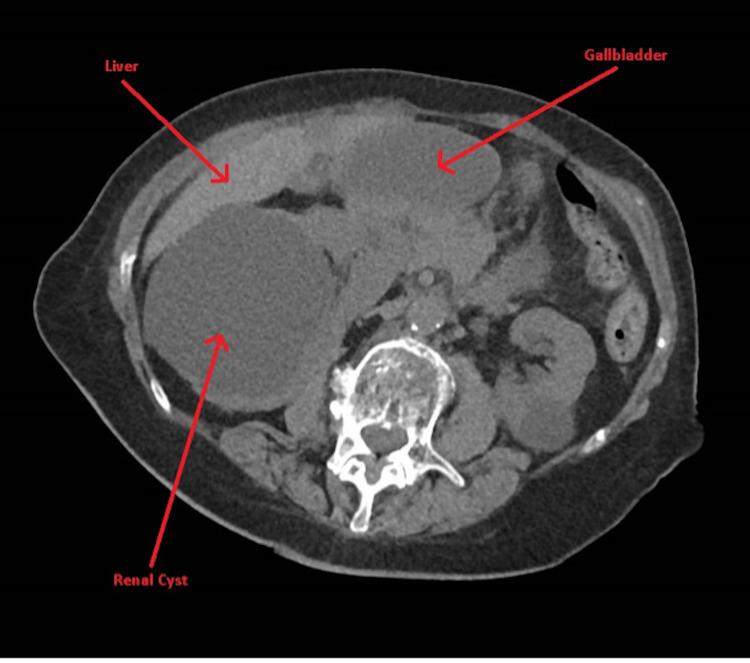

Gallbladder volvulus is a rarely reported and diagnosed condition. We present a case of an elderly female with right lower quadrant pain mimicking acute appendicitis without conclusive imaging; however, due to worsening serological laboratory findings and sepsis picture, an exploratory laparotomy was performed. A necrotic gallbladder was removed, diagnosing gallbladder volvulus. A systemic literature review showed the difficulty in making a diagnosis and the uniqueness of our patient presentation. A high level of clinical suspicion for gallbladder volvulus must be maintained and should be included in the differential diagnosis in elderly women with an acute abdomen, as complications can be severe.